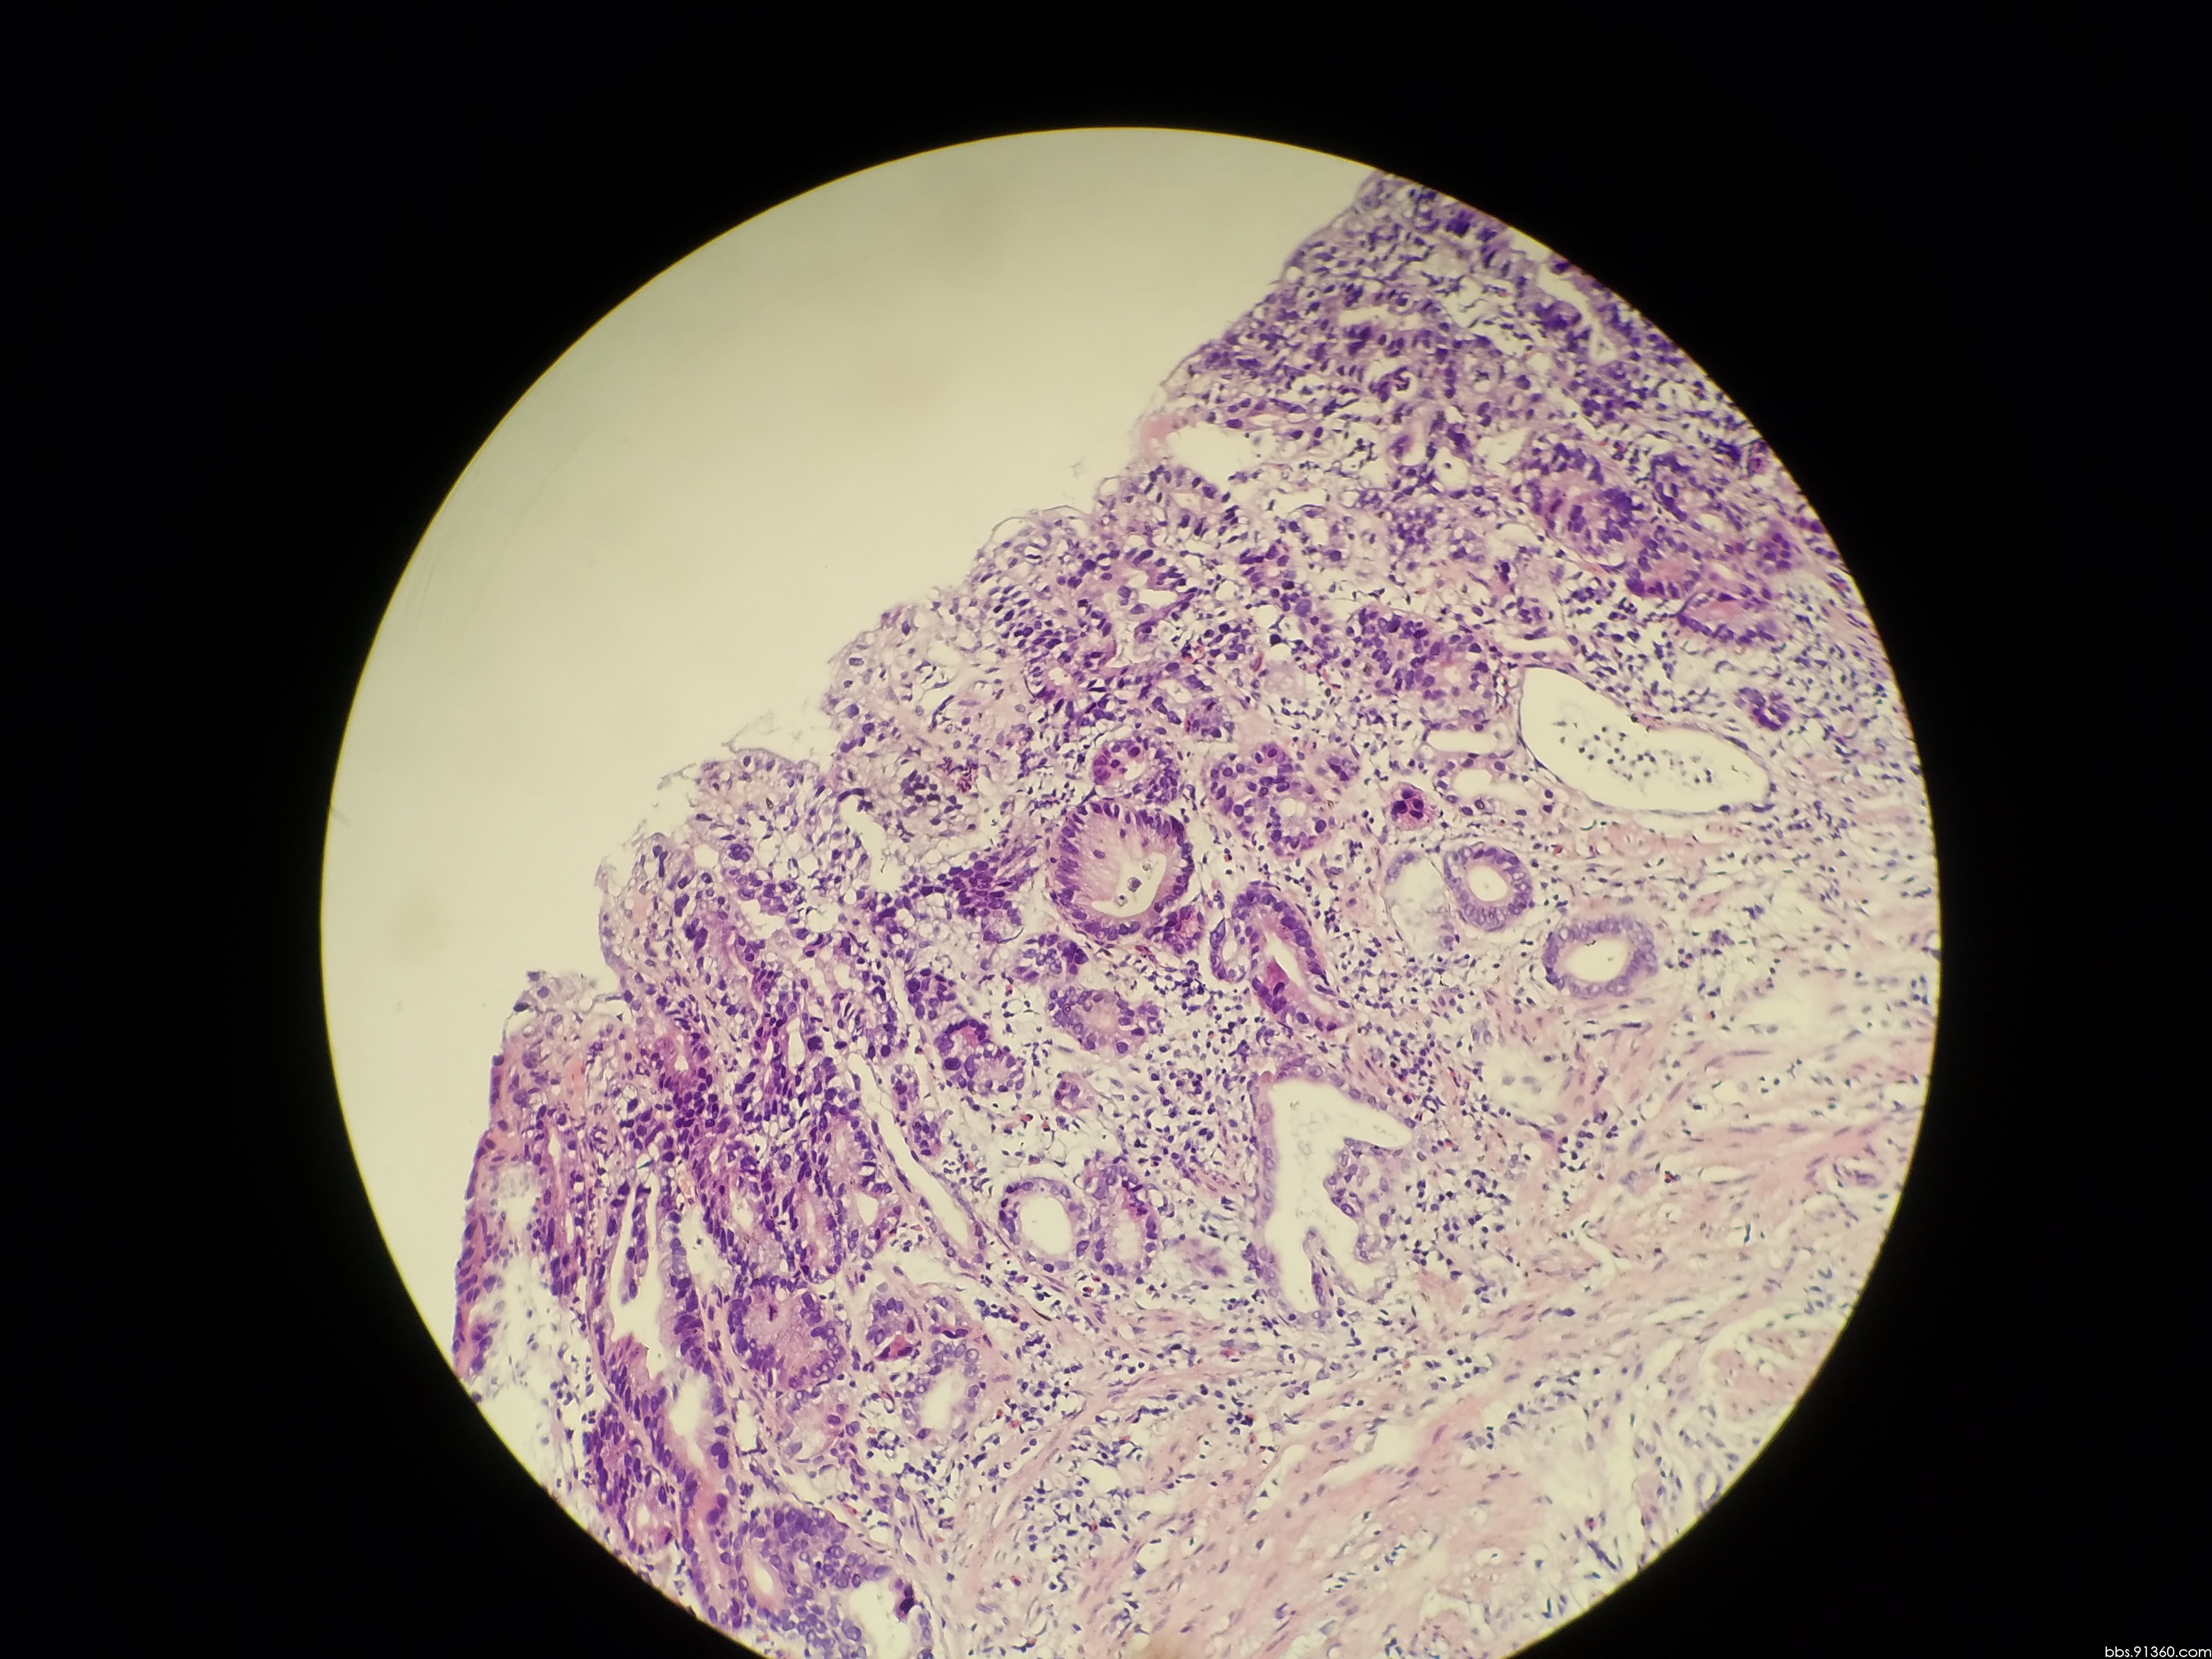

胃窦部黏膜组织活检镜下如图所示胃黏膜发生的有关病变的描述

胃窦部黏膜组织活检镜下如图所示胃黏膜发生的有关病变的描述错误的是

胃窦部黏膜活检

胃窦部黏膜活检

胃窦部黏膜活检

胃窦部黏膜活检